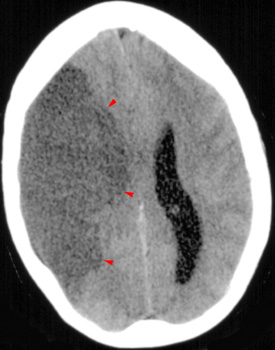

After a stroke, edema progresses, and brain density decreases proportionately. Severe ischemia results in a 3% increase in intraparenchymal water within 1 hour. This corresponds to 7-8 Hounsfield Unit decrease in brain density. There is also a 6% increase in water at 6 hours. The degree of edema is related to the severity of hypoperfusion and the adequacy of collateral vessels.